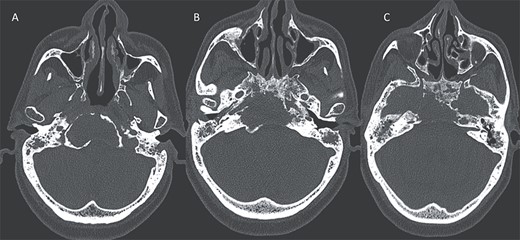

A computed tomography (CT) scan with intravenous contrast was performed (Figs 1 and 2), it revealed:

A 3 × 2.5 × 3.2 cm low-attenuating intra clival mass with peripheral enhancing, accompanied by extensive bone erosion of the clivus.

Bone destruction extending to the petrous, tympanic, and mastoid portions of the temporal bone, with involvement of the body and right greater wing of the sphenoid as well as the occipital bone, and concomitant sequestrum formations within the necrotic bones.

Presence of soft tissue in the middle ear cavity and in the mastoid cells.

(A) Axial CT in soft-tissue window showing an intra clival fluid collection (star). (B) Axial Post contrast CT showing a peripheral enhancement (arrow).

Axial CT in bony window showing: (A, B) extensive bone erosion of the clivus and the body and right greater wing of the sphenoid. (C) Soft tissue in the middle ear cavity and mastoid cells.